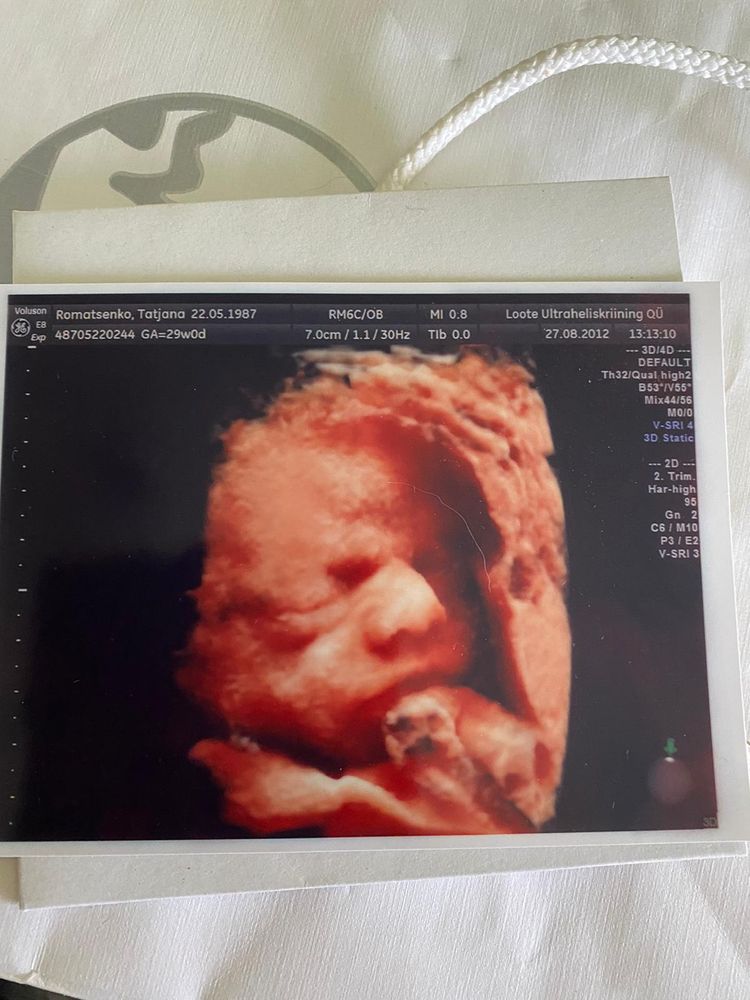

29 недель ходила, самое то

Чем быстрее тем лучше, не помню точно, но до 30-31 недели, кажется. Потом ребенку уже совсем тесно и картинки не получится. С дочкой ходили в 29 недель - идеально было

Надежда, с щёчками, и ещё какими 😅